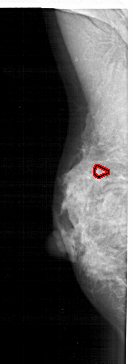

FILE: A_1283_1.LEFT_MLO.OVERLAY

TOTAL_ABNORMALITIES 1

ABNORMALITY 1

LESION_TYPE CALCIFICATION TYPE PUNCTATE DISTRIBUTION CLUSTERED

ASSESSMENT 4

SUBTLETY 1

PATHOLOGY MALIGNANT

TOTAL_OUTLINES 1

BOUNDARY